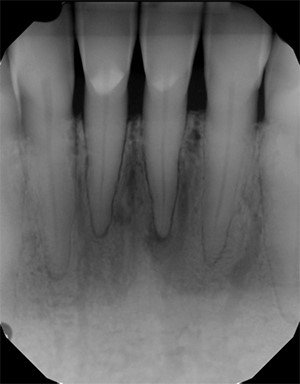

• periapikalinę radiogramą (2 pav.) – gali būti matomas dantų pūlinys, periodonto patologija;

2 pav. Periapikalinė radiograma (10)

Kartais, kai yra pašalintas uždegimą sukėlęs dantis ir įtariama, kad žandinis antis susijungia su burnos ertme, radiologinis tyrimas atliekamas su gutaperčios kaiščiu alveolėje (3). Uždegimui esant odontogeninės kilmės, ligą sukėlusio danties vainike bus stebimas danties ėduonis ar užpildas arti pulpos kameros. Stebimi ir periodonto radiologiniai pakitimai – padidėjęs ir išplatėjęs periodonto plyšys su kaulo destrukcija (3). Kartais antyje gali būti randama plombinės medžiagos ar lūžusių endodontinių instrumentų (2–4, 6). Pašalinus OŽS sukėlį dantį, žandiniam ančiui jungiantis su burnos ertme, matoma šio danties alveolė, nepripildyta kaulo, ir nevientisas, suardytas, su defektu žandinio ančio apatinės sienos radiologinis vaizdas. Atliktos žandinio ančio radiogramos yra lyginamos – dešinė yra lyginama su kaire (2). Radiologiniuose vaizduose stebimas gleivinės paburkimas, kuris gali būti lokalus, dėl pūlingo uždegimo matoma vadinamoji skysčio linija (3 pav.), užtemęs sinusas (2–4, 9).